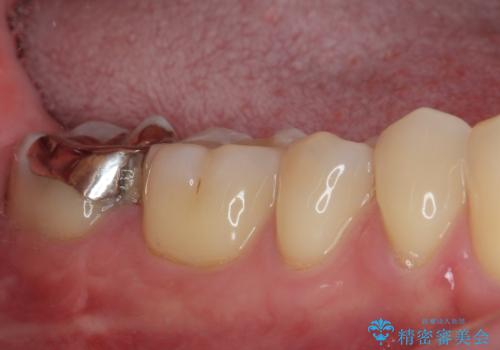

最後の確認方法として、局所麻酔を行わずに最後臼歯の銀歯を外し、神経組織近くまで歯質を切削したところ痛みなどを全く感じず、その後無菌的環境下にて切削を進めたところ、神経組織の一部が壊死していることが確認されました。

その後は速やかに根管治療を行い、初回の処置以降は痛みや違和感が一気に引いたため、根管治療後にオールセラミッククラウンにて補綴治療を行うこととしました。